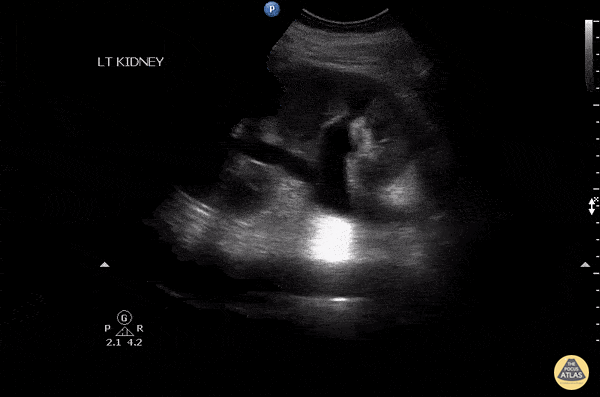

Patient with a history of hypertension presented with left flank pain and microhematuria. Kidney was scanned and revealed hydronephrosis without presence of a stone. Ultimately MRI was obtained and received a final diagnosis of idiopathic retroperitoneal fibrosis which was causing external compression of ureter. Image courtesy of Robert Jones DO, FACEP @RJonesSonoEM Director, Emergency Ultrasound; MetroHealth Medical Center; Professor, Case Western Reserve Medical School, Cleveland, OH View his original post here